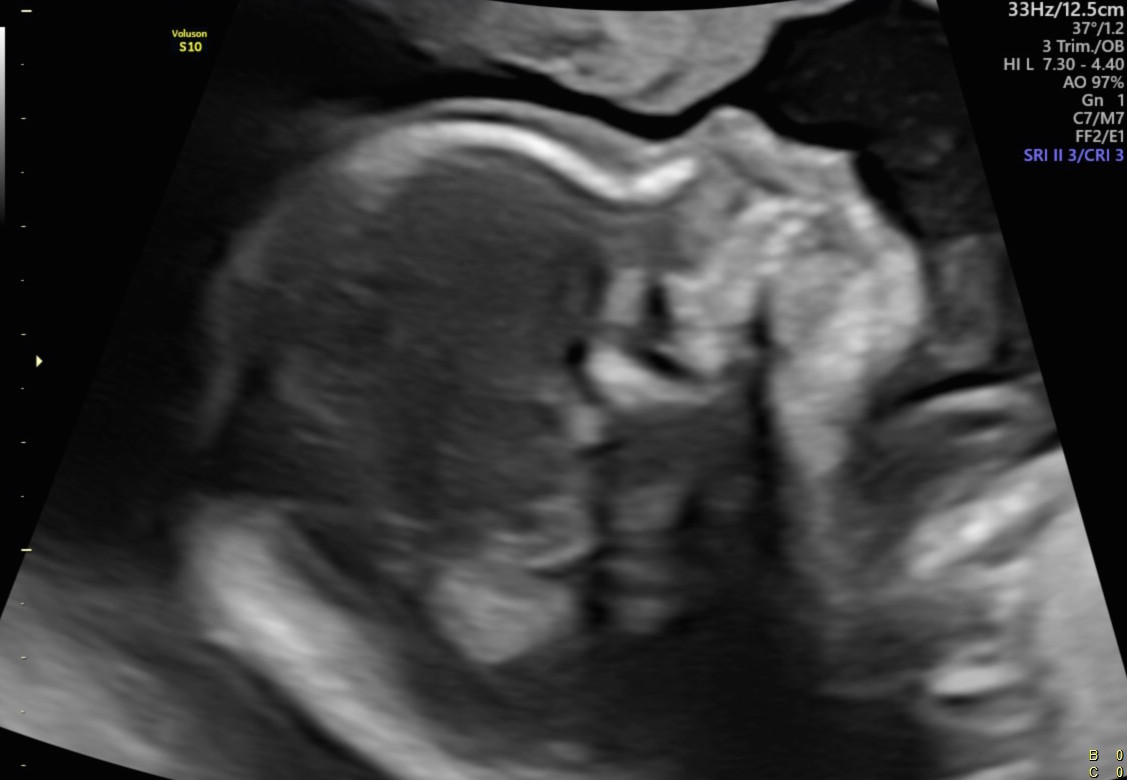

Se recibe en la consulta una paciente de 35 años secundigesta. Presenta como único antecedente de relevancia un recién nacido vivo de término con peso adecuado. Concurre cursando un embarazo de 22 semanas, para realizar el estudio morfológico detallado del segundo trimestre. Adjunta el resultado del screening del 1º trimestre que informa bajo riesgo para cromosomopatías y una ecografía obstétrica en semana 16 que informa crecimiento fetal adecuado para la edad gestacional, feto de sexo masculino, el resto sin particularidades. Ante los siguientes hallazgos, su diagnóstico presuntivo es a) Labio leporino unilateral con compromiso del reborde alveolar b) Labio leporino medial c) Labio leporino bilateral con fisura palatina d) Labio leporino bilateral, el reborde alveolar y el paladar impresionan indemne.

Respuesta correcta: c)Labio leporino bilateral con fisura palatina

A partir del segundo trimestre, el estudio ecográfico en 2D del labio y paladar se realiza evaluando tres planos: sagital, coronal y axial (Figs. 7-8-9-10).

En los casos de labio leporino bilateral o unilateral extenso, en cortes sagitales, se identifica la protrusión premaxilar compuesta por la porción central del labio superior y el paladar primario. La imagen es similar a la observada en el primer trimestre (Fig.11).

En el corte coronal modificado, en el que la punta de la nariz y la longitud del labio se ven en una misma vista, se puede evidenciar la interrupción de la superficie del labio y clasificar el defecto en unilateral (derecho o izquierdo) o bilateral (Fig. 12).